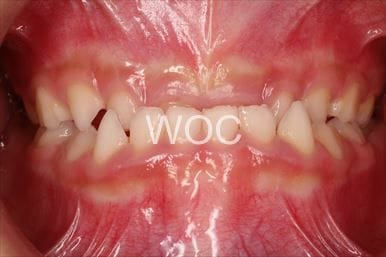

治療前1

-

治療前2

-

治療前3

- 年齢:32歳女性

- 主訴:前歯で噛めない

- 基本矯正料金:80万円

- 治療期間:1年11ヶ月

- 抜歯部位:上顎右側第一小臼歯、上顎左側第二小臼歯

-